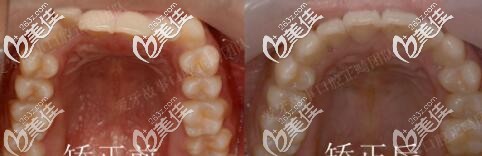

圖三咬合前后對(duì)比

矯正用了1年半,地包天明顯改善,牙弓也擴(kuò)開(kāi)了。正畸期間口腔護(hù)理很重要,如果出現(xiàn)了口腔有異味或炎癥,就要隔兩到三天使用牙套清潔片把牙套泡一泡,必要時(shí)可用酒精棉片對(duì)牙套進(jìn)行消毒。